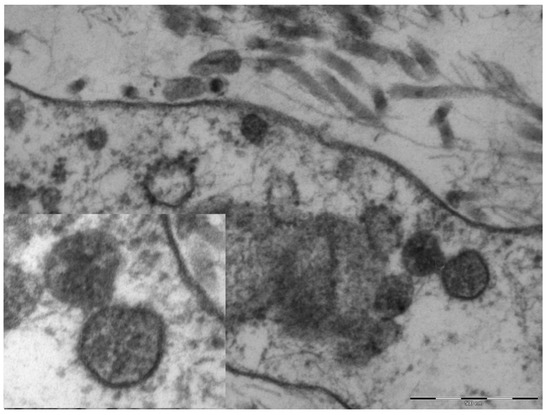

An electron microscopy study was performed in only one case, showing marked hypertrophy of the endothelial cells, the nuclei being characterized by finely distributed chromatin and retiform nucleoli. The cytoplasm contained very few organelles, with few small globular mitochondria. The fibroblasts were remarkably elongated and surrounded by very short collagen fibers. Spherical structures ranging from 65 to 136 nm were visible in the cytoplasm of endothelial cells and fibroblasts (Figure 4), characterized by a peripheral electron-dense rim and a clearer core. These structures were more frequently near the cell membrane or externally attached to it. Aggregates of multiple viral particles were grouped together close to phagosome-like vesicles. In some images, faintly electron-dense projections of different sizes (6–10 nm)—corresponding to the virus spikes—were visible, depicting a solar crown.

Figure 4.

Original magnification 89,000× fibroblast cytoplasm containing numerous maturing coronaviruses. Fragmented collagen fibers are visible in the interstice. In the box, 110,000×, whole virions are evident with spikes of different lengths and an electron-dense peripheral rim.